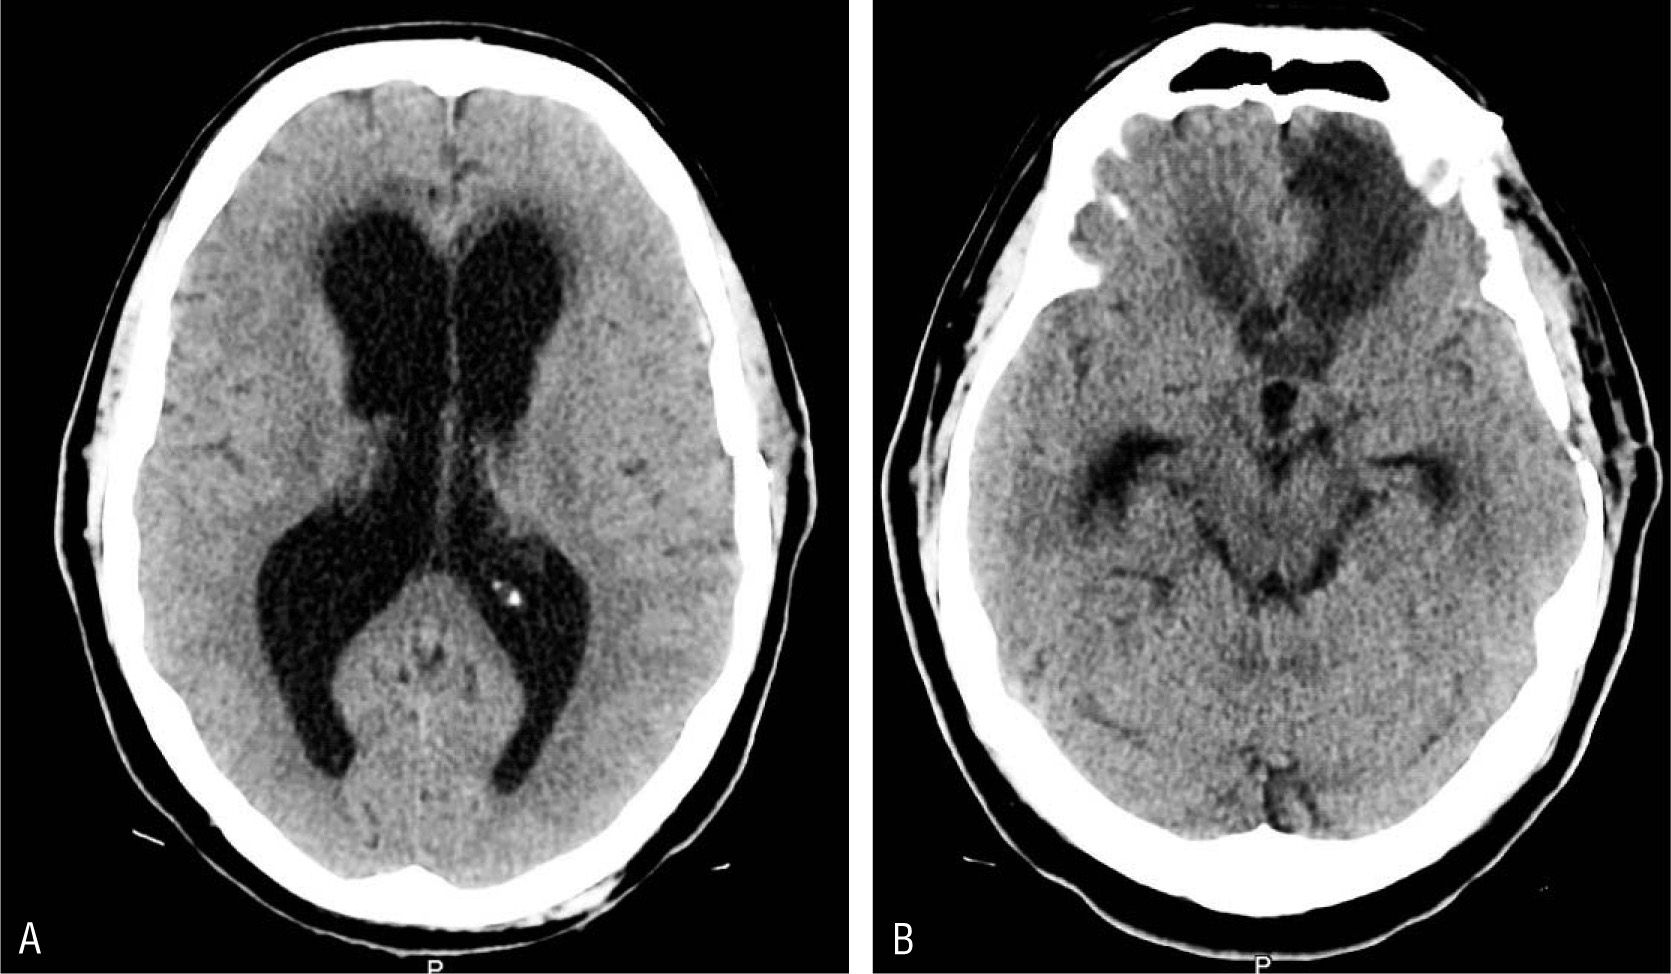

¿De qué se trata la hidrocefalia de presión normal? Se trata del aumento anormal del líquido cefalorraquídeo en las cavidades del cerebro. Sucede cuando el flujo de dicho líquido entre el cerebro y la médula espinal se obstruye de alguna manera. Cuando esto sucede, las cavidades o ventrículos aumentan de tamaño y ejercen mucha presión sobre el cerebro. En ocasiones puede ser el resultado de algún golpe traumático en la cabeza con hemorragia, de alguna infección, de un tumor o de complicaciones debidas a alguna cirugía.

Para establecer el diagnóstico preciso, el médico puede hacer varios exámenes detallados con imágenes del cerebro, tales como la tomografía computarizada o de resonancia magnética. También puede hacer una punción en la zona lumbar, medir la presión intracraneal y solicitar pruebas neuropsicológicas para descartar otros problemas.